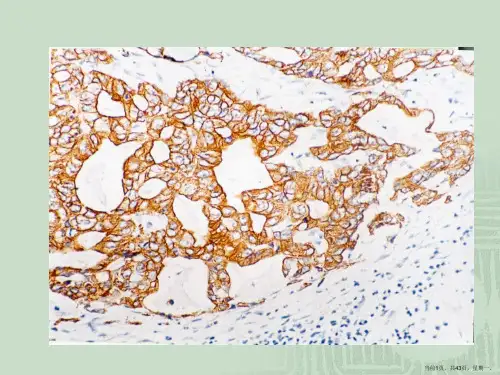

4. 染色结果,观察组织切片的染色结果,包括颜色强度、分布和细胞定位。

根据染色结果的强弱和分布情况,可以初步判断目标

蛋白在组织中的表达水平和分布情况。

1. 阳性结果:阳性结果表示目标蛋白质在组织或细胞中存在。

阳性结果可以分为强阳性、中阳性和弱阳性。

强阳性表示目标蛋白质的表达水平很高,中阳性表示表达水平适中,弱阳性表示表达水平较低。

阳性结果通常可以观察到明显的染色和强度,其分布模式可能是全细胞膜、核、细胞质等。

1. 强阳性(Strong positive):细胞或组织中存在大量的目标蛋白表达,通常显示为强烈的染色信号。

2. 中阳性(Moderate positive):细胞或组织中存在适度的目标蛋白表达,染色信号强度介于强阳性和弱阳性之间。

3. 弱阳性(Weak positive):细胞或组织中存在轻微的目标蛋白表达,染色信号强度较弱。

1. 强阳性(3+),细胞膜或细胞浆呈深褐色,且明显高于背景染色。

2. 中度阳性(2+),细胞膜或细胞浆呈较深的褐色,但略低于强阳性。

3. 弱阳性(1+),细胞膜或细胞浆呈浅褐色,仅略高于背景染色。